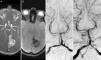

RM cerebral: A) Secuencia 3D de arterias intracraneales. B) Secuencia T2* axial que muestra un hematoma intraparenquimatoso en la región parietooccipital izquierda (* en A y B). Angiografía por sustracción digital: C y D) Vista anteroposterior que muestra un aneurisma sacular de 3mm en el segmento P4 distal de la ACP izquierda (arteria calcarina), antes de la embolización (flecha blanca en C) y después de la oclusión con coils (flecha blanca en D).

Se trata de una mujer de 40 años de edad sin antecedentes de interés, que consulta en urgencias por cefalea, inestabilidad, vómitos y visión borrosa de 24h de evolución. La exploración reveló la existencia de una hemianopsia homónima derecha sin otros déficits neurológicos. En la resonancia magnética cerebral y la angiografía por resonancia magnética solo se apreciaba la presencia de un hematoma intraparenquimatoso de localización parietooccipital izquierda sin otros hallazgos relevantes (fig. 1A y B). Puesto que esta era una localización poco frecuente para un hematoma en una paciente joven, se decidió completar el estudio mediante una angiografía para excluir una causa vascular subyacente. Este estudio se realizó 14 días después del inicio de los síntomas y reveló la presencia de un aneurisma de morfología sacular, con 3mm de diámetro máximo, en el segmento P4 distal de la ACP izquierda (arteria calcarina) (fig. 1C). A pesar de tratarse de un aneurisma de localización atípica, la ausencia de fiebre durante toda la hospitalización, ausencia de soplos cardiacos o de cualquier fenómeno embolico arterial, hacían poco probable el origen endocardítico del mismo. Con respecto al manejo, se optó por tratamiento endovascular, bajo anestesia general, en la sala de radiología neurointervencionista. El acceso se realizó a través de una punción femoral y el catéter guía se colocó en la arteria vertebral izquierda. Se logró una oclusión total del aneurisma mediante la liberación controlada de coils por vía endovascular. Una vez finalizada la embolización se obtuvieron imágenes angiográficas de control donde pudo comprobarse la permeabilidad de la arteria principal y la oclusión completa del aneurisma (fig. 1D). El postoperatorio transcurrió sin complicaciones y fue dada de alta 4 días después del procedimiento persistiendo la hemianopsia. En el seguimiento, 3 meses después del alta persistía déficit parcial del hemicampo visual derecho, con mejoría clínica, sin haber sufrido complicaciones en relación al aneurisma o a su tratamiento.